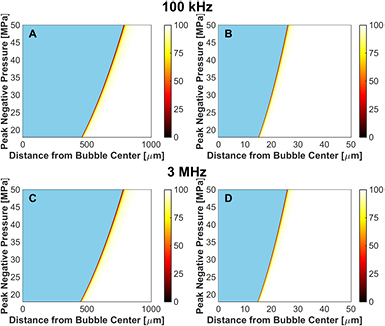

The viability of red blood cells is shown as a function of distance from the bubble wall for microtripsy excitations in figure 9, and for a single-cycle shock-scattering histotripsy excitation in figure 10. Strains were computed analytically at the maximum bubble diameter for Kelvin–Voight elasticity. The red blood cell viability increased rapidly from 0% at the bubble wall to 100% within 50 µm for all insonation conditions. The red blood cell viability increased sigmoidally as a function of distance away from the bubble wall, and was fit to a function of the form:

Figure 9. Microtripsy-induced reduction in red blood cell viability due to bubble expansion, reported in terms of percent viability in the colorbar. The fundamental frequency of the insonation was 100 kHz for the left column, and 3 MHz for the right column. The elastic modulus was 1 kPa for panels (A) and (B), and 1 MPa for panels (C) and (D). The initial bubble diameter was 5 nm. The regions in blue represent the extent of the bubble.

Download figure:

Standard image High-resolution imageFigure 10. Shock-scattering histotripsy-induced reduction in red blood cell viability due to bubble expansion, reported in terms of percent viability in the colorbar. The fundamental frequency of the insonation was 100 kHz for the left column, and 3 MHz for the right column. The elastic modulus was 1 kPa for panels (A) and (B), and 1 MPa for panels (C) and (D). The initial bubble diameter was 20 nm. The regions in blue represent the extent of the bubble.

Download figure:

Standard image High-resolution imageThe frequency, pressure, and elasticity dependence of r50 had a similar form to that for the maximum bubble size, as indicated in figure 11. For a medium with elastic modulus greater than 20 MPa, r50 approached 0 µm as bubble expansion was completely suppressed. For fixed medium elasticity and insonation conditions (peak negative pressure and fundamental frequency), r50 was greater for microtripsy pulses than shock scattering histotripsy pulses (table 3). Thus, the distance over which bubble expansion effects red blood cell viability is greater for microtripsy compared to shock scattering histotripsy. For fundamental frequencies greater than 1 MHz, changes in red blood cell viability did not extend beyond 5 µm, roughly the size of a red blood cell (Lewis 1996).

Standard image High-resolution imageChanges in cell viability induced by strain from the bubble collapse are shown in figure 12. While strain during the expansion pushes red blood cells away from the bubble, strain during collapse pulls the red blood cells toward the bubble. For conditions of massive bubble expansion (i.e. medium elasticity less than 20 MPa), the cell viability at a fixed distance from the bubble varied by less than 0.1% over the range of media elasticity or insonation conditions considered in this study. Bubble collapse-induced changes in cell viability appear to be restricted within 2 nm for microtripsy excitations, and 10 nm for shock scattering histotripsy.

Figure 12. Change in cell viability, expressed in terms of percent in the colorbar, due to strain at minimum bubble radius for microtripsy insonation (left column) and shock-scattering histotripsy insonation (right column) for medium elastic modulus of 1 kPa (panels (A) and (B)) and 1 MPa (panels (C) and (D)). The fundamental frequency of the insonation was 1 MHz for both calculations, and the initial bubble diameter was 5 nm for the microtripsy excitation and 20 nm for the shock scattering histotripsy excitation.

4.4. Prediction of red blood cell viability

Red blood cell viability surrounding histotripsy cavitation activity was modeled based on measurements of impulsive stretching of erythrocytes (Li et al 2013). Strain fields surrounding the bubble were rapidly attenuated within 50 µm from the bubble wall, consistent with previous calculations of histotripsy-induced cavitation (Mancia et al 2017). Only red blood cells within a few micrometers from the bubble wall experienced lethal strain (table 3), and the erythrocyte viability increased sigmoidally with distance away from the bubble. On a macroscopic level, the limited distance over which red blood cell viability is reduced observed in this study is consistent with the sharp boundaries observed in histotripsy lesions (Parsons et al 2006, Kieran et al 2007, Vlaisavljevich et al 2013a, Darnell et al 2015). In vitro studies have demonstrated histotripsy-induced breast cancer cell bisection occur only within a few micrometers to a nucleated bubble (Vlaisavljevich et al 2016). Under the similar insonation conditions, the calculations in this study indicate changes in red blood cell viability would be restricted within 1 µm of the bubble (figures 11(C) and (E)).

In media stiffer than 20 MPa, calculations indicate the strain on erythrocytes is insufficient to induce lysis for the histotripsy insonation parameters considered (figure 11). In softer media, the extent of damage beyond the bubble volume was found to depend on the insonation type. Microtripsy-nucleated bubbles induce larger strains at greater distances from the bubble compared to shock scattering cavitation for a given set of insonation parameters. Depending on the necessity for precision relative to the observed spatial location of the bubble cloud, the choice of insonation scheme should be considered.